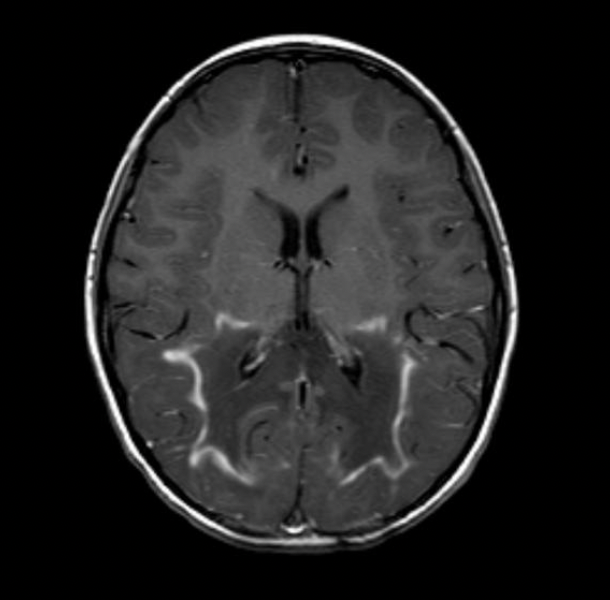

Imagem 2

Intoxicação pelo metotrexate